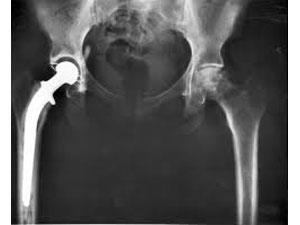

கடந்த சில வாரக்களுக்கு முன்னர், மணிக்யம் தெருவில் சென்று கொண்டிருந்த போது நாய் ஒன்று துரத்தியதில் கீழே விழுந்து இடுப்பில் அடி பட்டது. அவரைப் பரிசோதித்த செகந்தராபாத்தில் உள்ள அபோல்லோ மருத்துவமனை மருத்துவர்கள் அவரது இடது பக்க இடுப்பெலும்பு மூட்டு உடைந்து விட்டதாக தெரிவித்துள்ளனர்.

103 வயதான அவருக்கு மயக்க மருந்து கொடுப்பதே மிகவும் சவாலான காரியமாக இருந்தபோதும், கட்டாயம் அறுவைச் சிகிச்சை செய்தே ஆக வேண்டிய கட்டாயத்தில் இருந்தது அவரது உடல்நிலை. மணிக்யத்தின் உயிரை காப்பாற்ற வேண்டிய நிர்பந்தத்தில் இதை ஒரு சவாலாக எடுத்துக் கொண்டு, டாக்டர் மிதின் அசியுடன் இணைந்த மருத்துவர் குழு ஒன்று, அவருக்கு இடுப்பு எலும்பு மாற்று அறுவை சிகிச்சையை வெற்றிகரமாக நடத்திக் காட்டியுள்ளது.

அறுவைச் சிகிச்சைக்குப் பிறகு மணிக்யத்திற்கு லேசான ரத்த அழுத்தம், கண்பார்வைக் கோளாறு தவிர உடல் கோளாறு எதுவும் இல்லை என்று தெரிவித்த மருத்துவர்கள் அவர் விரைவில் பூரண குணமடைவார் என்றும் நம்பிக்கைத் தெரிவித்துள்ளனர்.